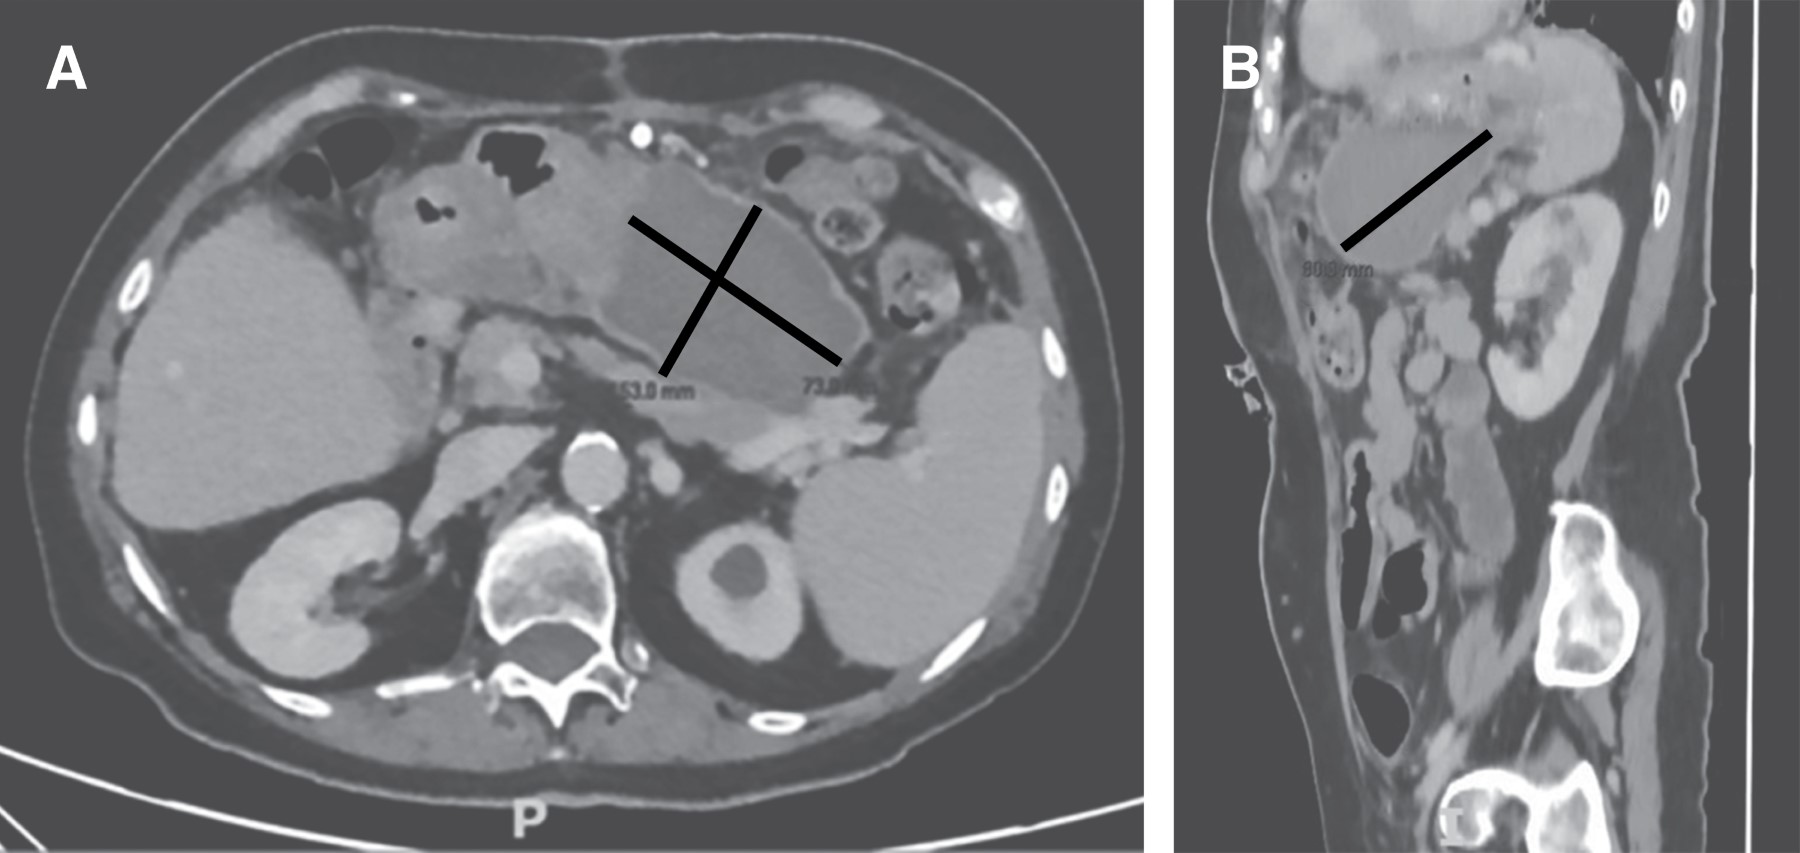

Al segundo día postoperatorio la paciente egresa a piso de hospitalización sin complicaciones, con pruebas de función hepática a la baja y tomografía axial computarizada (TAC) de control con evidencia del segmento IV con aumento de volumen, sin flujo vascular, sin datos de complicación actual (Figura 1).

Figura 1